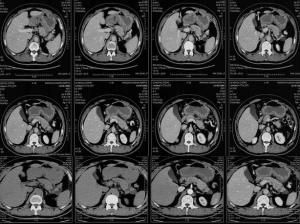

3.CT檢查

CT能準確地顯示胰腺囊腫的部位,大小,測定囊壁的厚度,囊內容物的密度,探知有無囊內間隔或囊內新生物,了解囊腫與周圍臟器,重要血管的相互關係,能為診斷和治療提供充分的參考資料,特別對於肥胖或胃腸道脹氣,B超不能正確診斷的病人,CT更顯示其優越性。